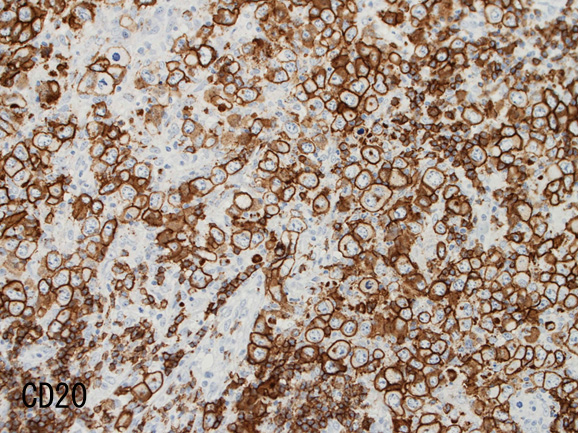

免疫染色†

腫瘍細胞はCD20+, CD30+, CD15-, PAX-5+, Oct.2+, BOB.1+(Oct2, BOB1は田丸先生の染色結果), EBER-ISH+, EBNA2-

| CD20 | PAX-5 | CD30 | EBER-ISH+ |